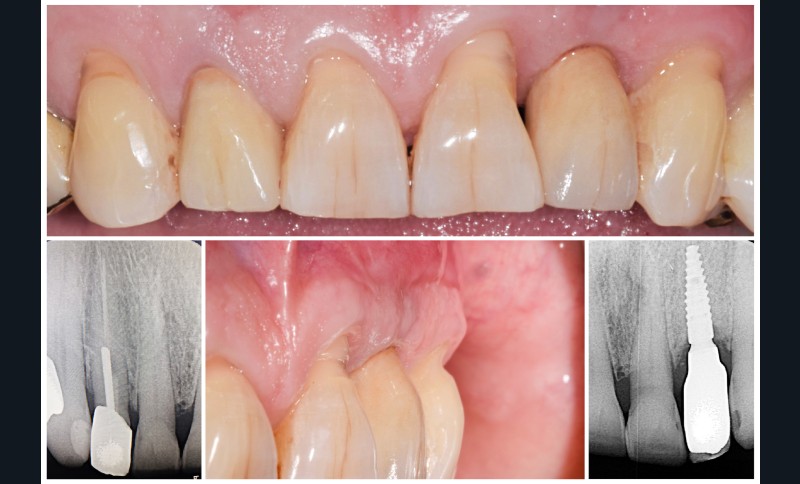

Au vu des conditions initiales, il nous apparaît impossible de restaurer une esthétique satisfaisante, notamment au niveau de l’alignement des collets, sans une chirurgie muco-gingivale associée à une réhabilitation des dents antérieures par facettes. En effet, la perte de la 22, associée à une forme triangulaire des dents, a provoqué un non-alignement des collets ainsi que la présence de trous noirs entre les dents 21-22 et 22-23. Cependant, les contraintes exprimées par le patient contre-indiquaient ce traitement.

La proposition thérapeutique retenue par le patient est donc une réhabilitation par couronne céramique sur 12 (dento-portée) et 22 (implanto-portée). Ce choix thérapeutique impose de concevoir des dents qui s’intègrent au mieux dans l’harmonie du sourire, tout en étant conscient des limites d’un tel traitement.